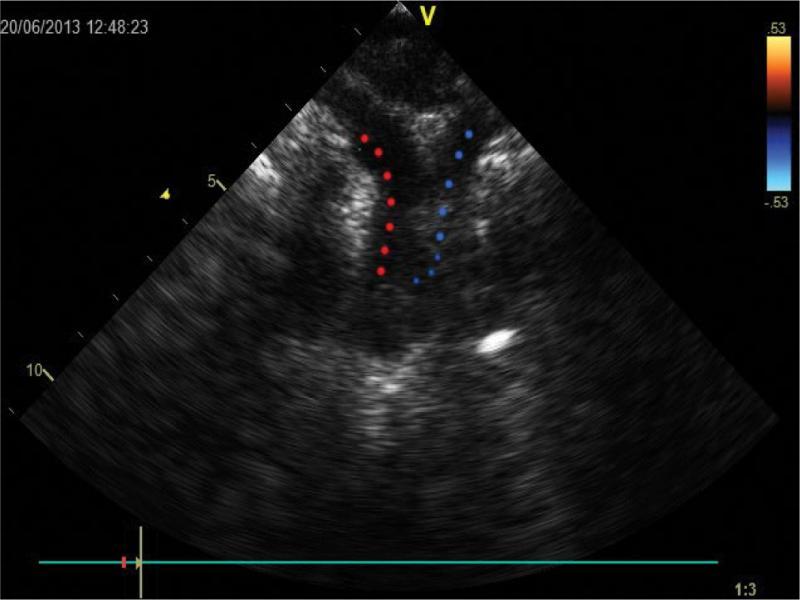

Cross-section in a plane close to frontal (with slight head rotation). Visible proximal part of the aortic arch (Ao) and its transverse section; a vertically running vein (V) crosses posteriorly the left pulmonary artery (LPA) and the descending aorta. Multiple respiratory artefacts obscuring the view of vascular flow. LA – left atrium, RPA – right pulmonary artery